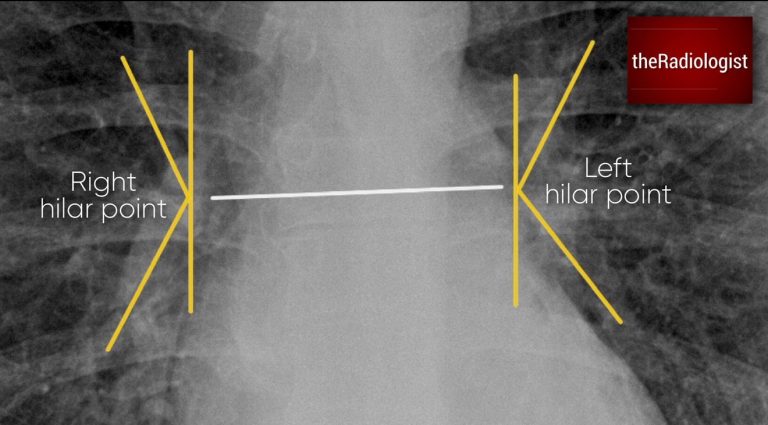

Assess three things: the position, morphology and density of the hila. To assess the position, draw in the ‘hilar point’ the point at which the hilar vessels intersect. The left can sit up to 2 cm higher than the right, but the right should never be higher: if position rules aren’t obeyed there could be collapse of a lobe or localised fibrosis.

Draw in the hilar points: the place where the hilar vessels intersect. The left can sit up to 2 cm higher than the right but the right should not be higher. If these rules are not obeyed consider lobar collapse or focal fibrosis.